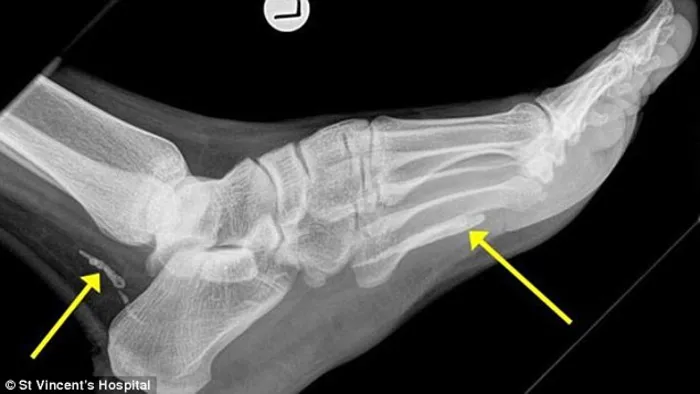

Metre-long worm living in foot for at least four years

Buried at the back of his ankle and the front of his sole, the disintegrated parts of a metre long worm...